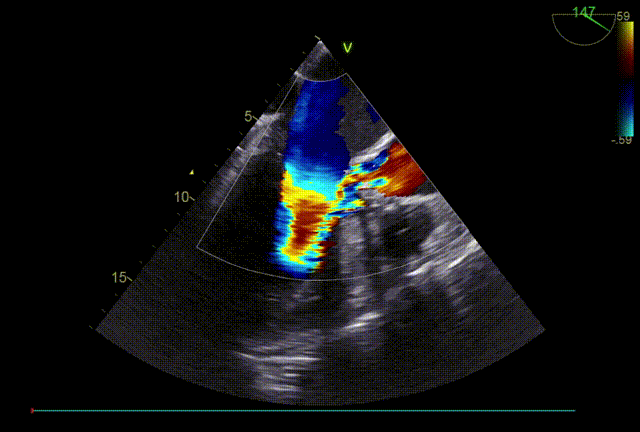

TTE